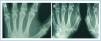

En enero de 2006, presentó HPTS grave (con niveles más elevados de iPTH que los presentados en los meses anteriores). La ecografía paratiroidea reveló una imagen seudonodular hiperecogénica en la zona posteromedial del lóbulo tiroideo izquierdo, que era compatible con una hipertrofia de la glándula paratiroidea. Una serie radiológica mostró signos de hiperparatiroidismo en los huesos de ambas manos y muñecas y CV en las arterias radiales e interdigitales. En la mamografía se observaron múltiples CV lineales en ambas mamas (figura 1A, figura 2A, figura 3A y figura 4A; imágenes de las manos y de las glándulas mamarias en 2006).

Durante este período, se pudo observar que en la serie radiológica las calcificaciones de la arteria interdigital habían desaparecido y que el hueso presentaba un aspecto más estructurado (figura 1B y figura 2B; imagen de la mano, 2007). También la mamografía mostró una regresión de las CV. Las calcificaciones lineales iniciales fueron sustituidas por calcificaciones irregulares (figura 3B y figura 4B; glándulas mamarias en 2007).

Figura 1. (A) Imagen radiográfica anteroposterior de la mano izquierda en el año 2006. (B) Imagen radiográfica anteroposterior de la mano izquierda en el año 2007.

Figura 2. (A) Imagen radiográfica anteroposterior de la mano derecha en el año 2006. (B) Imagen radiográfica anteroposterior de la mano derecha en el año 2007.